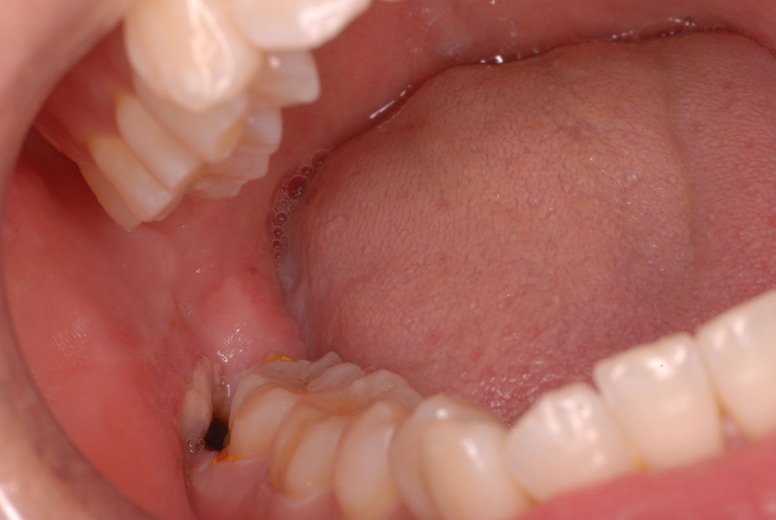

写真左下の親知らずが痛くなり抜歯しました。その後歯茎を除去して虫歯を露出させる処置を二回ほどしています。

レントゲンでは小さいですが、こう言う虫歯が一番怖いのです。

治療の成功率は極めて悪くすぐ再発しやすいのです。